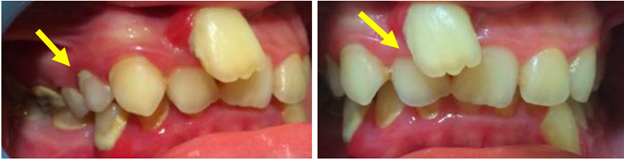

Figure 7 A&B No interproximal reduction (IPR) was needed here in the mandibular arch as the volumetric change in the alveolar bone growth in the maxillary incisor premaxilla area and especially around the maxillary right lateral, help correct the anterior crossbites/underbite. This may not be the case in more severe underbites and IPR may be needed.

However, it is important to provide additional context regarding the initial treatment approach, which involved a gingival graft to address the periodontal dehiscence. However, by forgoing traditional periodontal treatment and opting for an orthodontic alveolar bone restoration protocol with FASTBRACES® Technologies, partial coverage of the exposed tooth by alveolar bone was achieved. This suggests the convergence and potential overlap between periodontics and orthodontic alveolar bone restoration, highlighting the need for interdisciplinary collaboration. A FASTBRACES® Technologies intervention restores alveolar bone architecture, naturally aligns the teeth thereby also altering the highly pathogenic microbial flora. This is because the universal constant is the alveolar bone clinical morphology with treatment directed towards the alveolar bone deficiencies when present. These four cases are successful examples of non- extraction orthodontic treatment with the patented systems of FASTBRACES® Technologies which appropriately address the relevant deficiencies in the alveolar bone clinical morphology while maintaining a 1 to 3mm overbite /overjet and not changing the patient’s natural molar relation. The authors believe the systems of FASTBRACES® Technologies induce alveolar bone remodeling by moving the tooth roots towards their natural properly erupted positions from the onset of treatment.